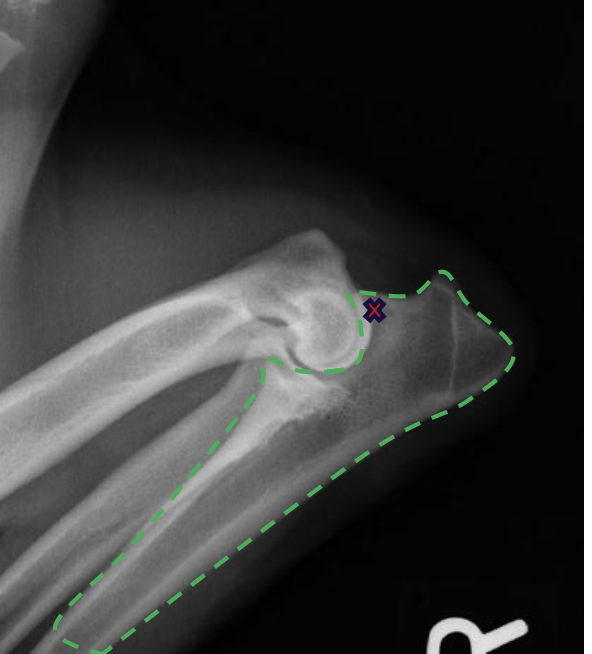

what is the red X marking?

anconeal process of the ulna

what radiographic view of the elbow is shown?

lateral view with elbow flexed 90 degrees

lateral view with elbow fully flexed

what structure of the elbow is focused on if we are doing a lateral view with the joint fully flexed?

olecranon process